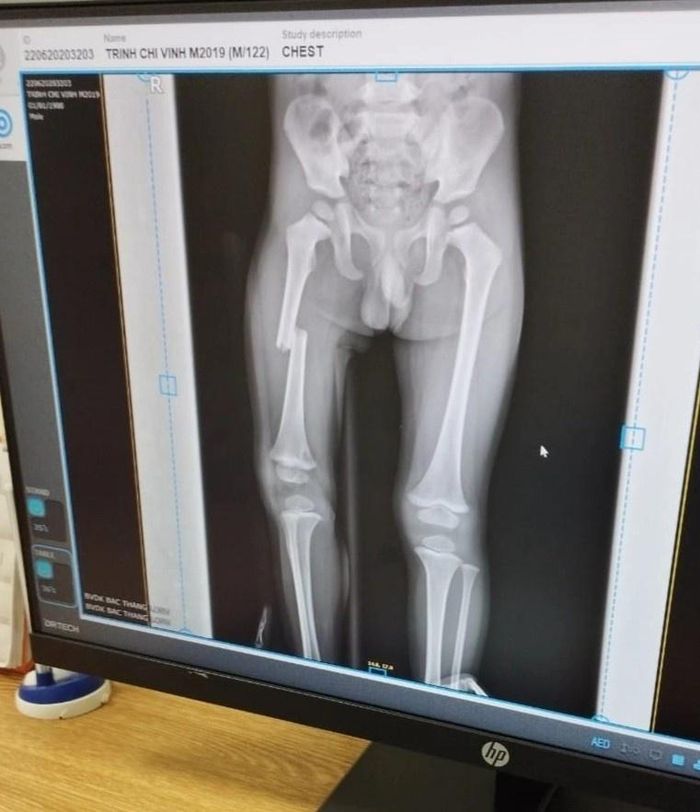

Ảnh chụp X-quang xương chân cháu bé. Ảnh: Gia đình cung cấp.

Chiều 23/9, lãnh đạo Công an huyện Lục Ngạn, tỉnh Bắc Giang, cho biết đơn vị đang điều tra, xác minh vụ một bé trai bị mẹ đạp gãy xương đùi xảy ra tại xã Quý Sơn. Cơ quan công an đã mời những người liên quan đến làm việc, trong đó có mẹ của bé trai. Về tình trạng sức khỏe của cháu bé, lãnh đạo công an huyện cho biết nạn nhân đã bình phục, có thể đi học bình thường.